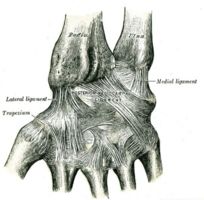

Ligaments: posterior view of left wrist